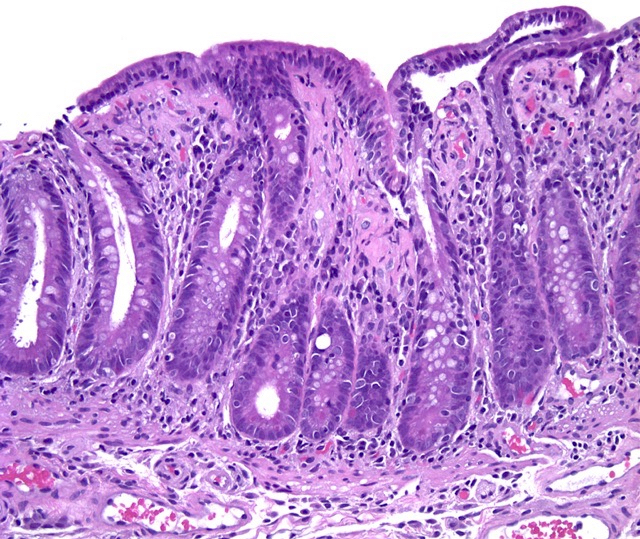

Microscopic (histologic) description

- Histological elementary lesions (Dig Liver Dis 2011;43:S385, Semin Diagn Pathol 2014;31:124):

- Increased intraepithelial T lymphocytes (IEL):

- 25 - 29 IEL/100 enterocytes is considered borderline

- > 30 IEL/100 enterocytes represents a pathological lymphocytosis

- Decreased enterocyte height, flattening of enterocytes, intracytoplasmic vacuolation and reduction or absence of brush border are suggestive but not specific

- Crypt hyperplasia:

- Extension of the regenerative epithelial crypts associated with changes in the presence of more than 1 mitosis per crypt

- Villous atrophy:

- Decrease in villous height, normal villous:crypt ratio (3:1) until total disappearance of villi

- This assessment requires proper orientation of the biopsies

- Increased intraepithelial T lymphocytes (IEL):

- Diagnostic categories are based on these elementary lesions:

- Modified Marsh-Oberhuber classification of histologic findings in celiac disease

- Simplified systems (Corazza & Villanaci or Ensari), which may be more reproducible (Arch Pathol Lab Med 2010;134:826, Pathol Res Pract 2016;212:1174)

- Different grades of duodenal mucosal lesions:

- Grade A / type 1: increased intraepithelial lymphocytes but no villous atrophy

- Grade B1 / type 2: villi still present but shortened

- Grade B2 / type 3: complete villous atrophy

Microscopic (histologic) images